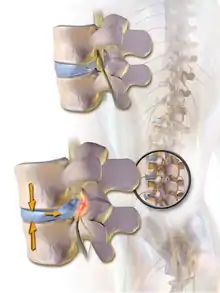

Spinal fusion, also called spondylodesis or spondylosyndesis, is a surgery performed by orthopaedic surgeons or neurosurgeons that joins two or more vertebrae.[1] This procedure can be performed at any level in the spine (cervical, thoracic, lumbar, or sacral) and prevents any movement between the fused vertebrae. There are many types of spinal fusion and each technique involves using bone grafting—either from the patient (autograft), donor (allograft), or artificial bone substitutes—to help the bones heal together.[2] Additional hardware (screws, plates, or cages) is often used to hold the bones in place while the graft fuses the two vertebrae together. The placement of hardware can be guided by fluoroscopy, navigation systems, or robotics.

Spinal fusion is most commonly performed to relieve the pain and pressure from mechanical pain of the vertebrae or on the spinal cord that results when a disc (cartilage between two vertebrae) wears out (degenerative disc disease).[3] It is also used as a backup procedure for total disc replacement surgery (intervertebral disc arthroplasty), in case patient anatomy prevents replacement of the disc. Other common pathological conditions that are treated by spinal fusion include spinal stenosis, spondylolisthesis, spondylosis, spinal fractures, scoliosis, and kyphosis.[3]

The most common cause of pressure on the spinal cord/nerves is degenerative disc disease.[6] Other common causes include disc herniation, spinal stenosis, trauma, and spinal tumors.[4] Spinal stenosis results from bony growths (osteophytes) or thickened ligaments that cause narrowing of the spinal canal over time.[4] This causes leg pain with increased activity, a condition called neurogenic claudication.[4] Pressure on the nerves as they exit the spinal cord (radiculopathy) causes pain in the area where the nerves originated (leg for lumbar pathology, arm for cervical pathology).[4] In severe cases, this pressure can cause neurologic deficits, like numbness, tingling, bowel/bladder dysfunction, and paralysis.[4]